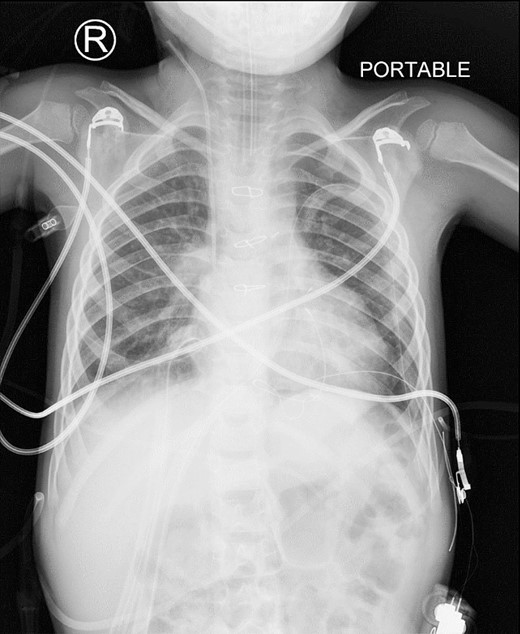

A preoperative assessment revealed an unexpected diaphragmatic hernia found incidentally on a routine chest X-ray (Fig. 1). This led to further tests, including a chest computed tomography (CT), which showed a central diaphragmatic defect with part of the transverse colon herniated into the chest (Fig. 2). Additionally, echocardiography found a perimembranous VSD with bidirectional shunting and mild tricuspid valve regurgitation. Cardiac catheterization confirmed reactive pulmonary vascular resistance.

This is a preoperative chest X-ray with an AP view revealing subtle lucent mediastinal structures in the lower mid-chest.